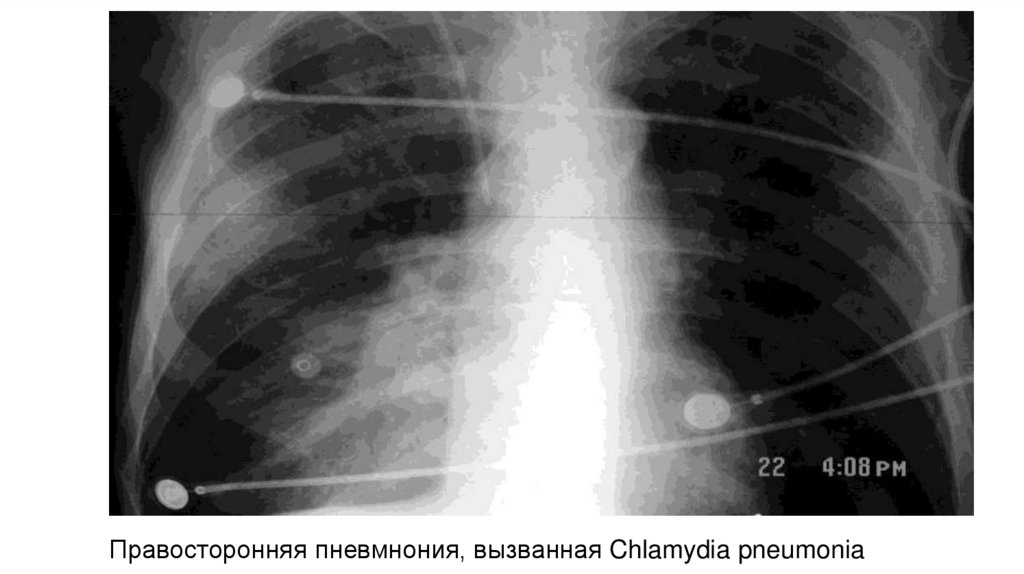

Правосторонняя пневмнония, вызванная Chlamydia pneumonia